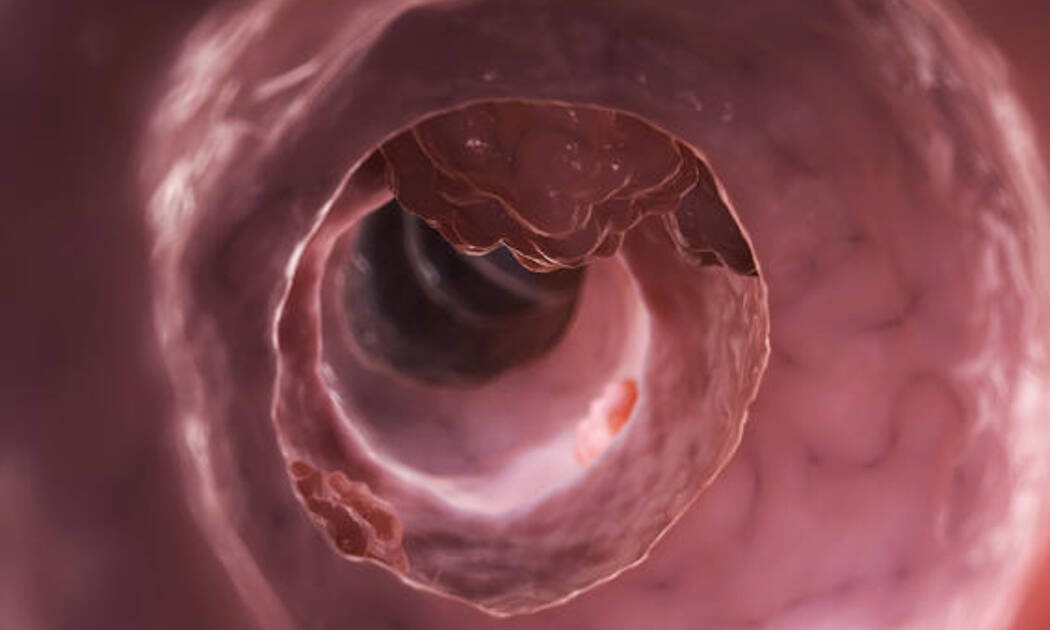

Καρκίνος εντέρου: Ποιες είναι οι ηλικίες που χτυπάει συχνότερα (αναλυτικά)

Τα ποσοστά εμφάνισης καρκίνου του εντέρου σε άτομα κάτω των 50 ετών έχουν αυξηθεί σημαντικά τα τελευταία χρόνια σε πολλές αναπτυγμένες χώρες.